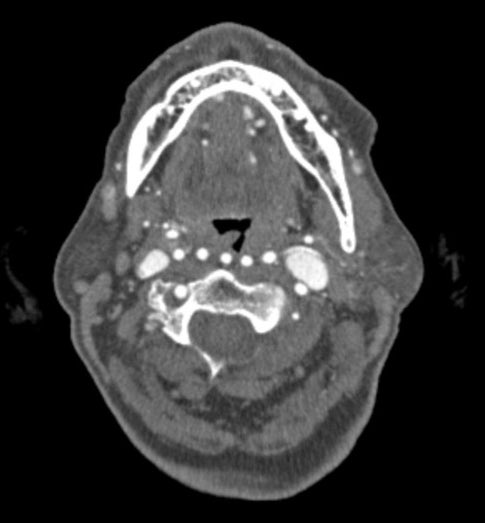

Stuff ENT nightmares are made of. Hope no one does a tonsillectomy or adenoidectomy on this patient…

1, 2 , 3, 4… wait, what? radiopaedia.org/cases/97452 @Radiopaedia case by Dr Ahmed A. Khawwam